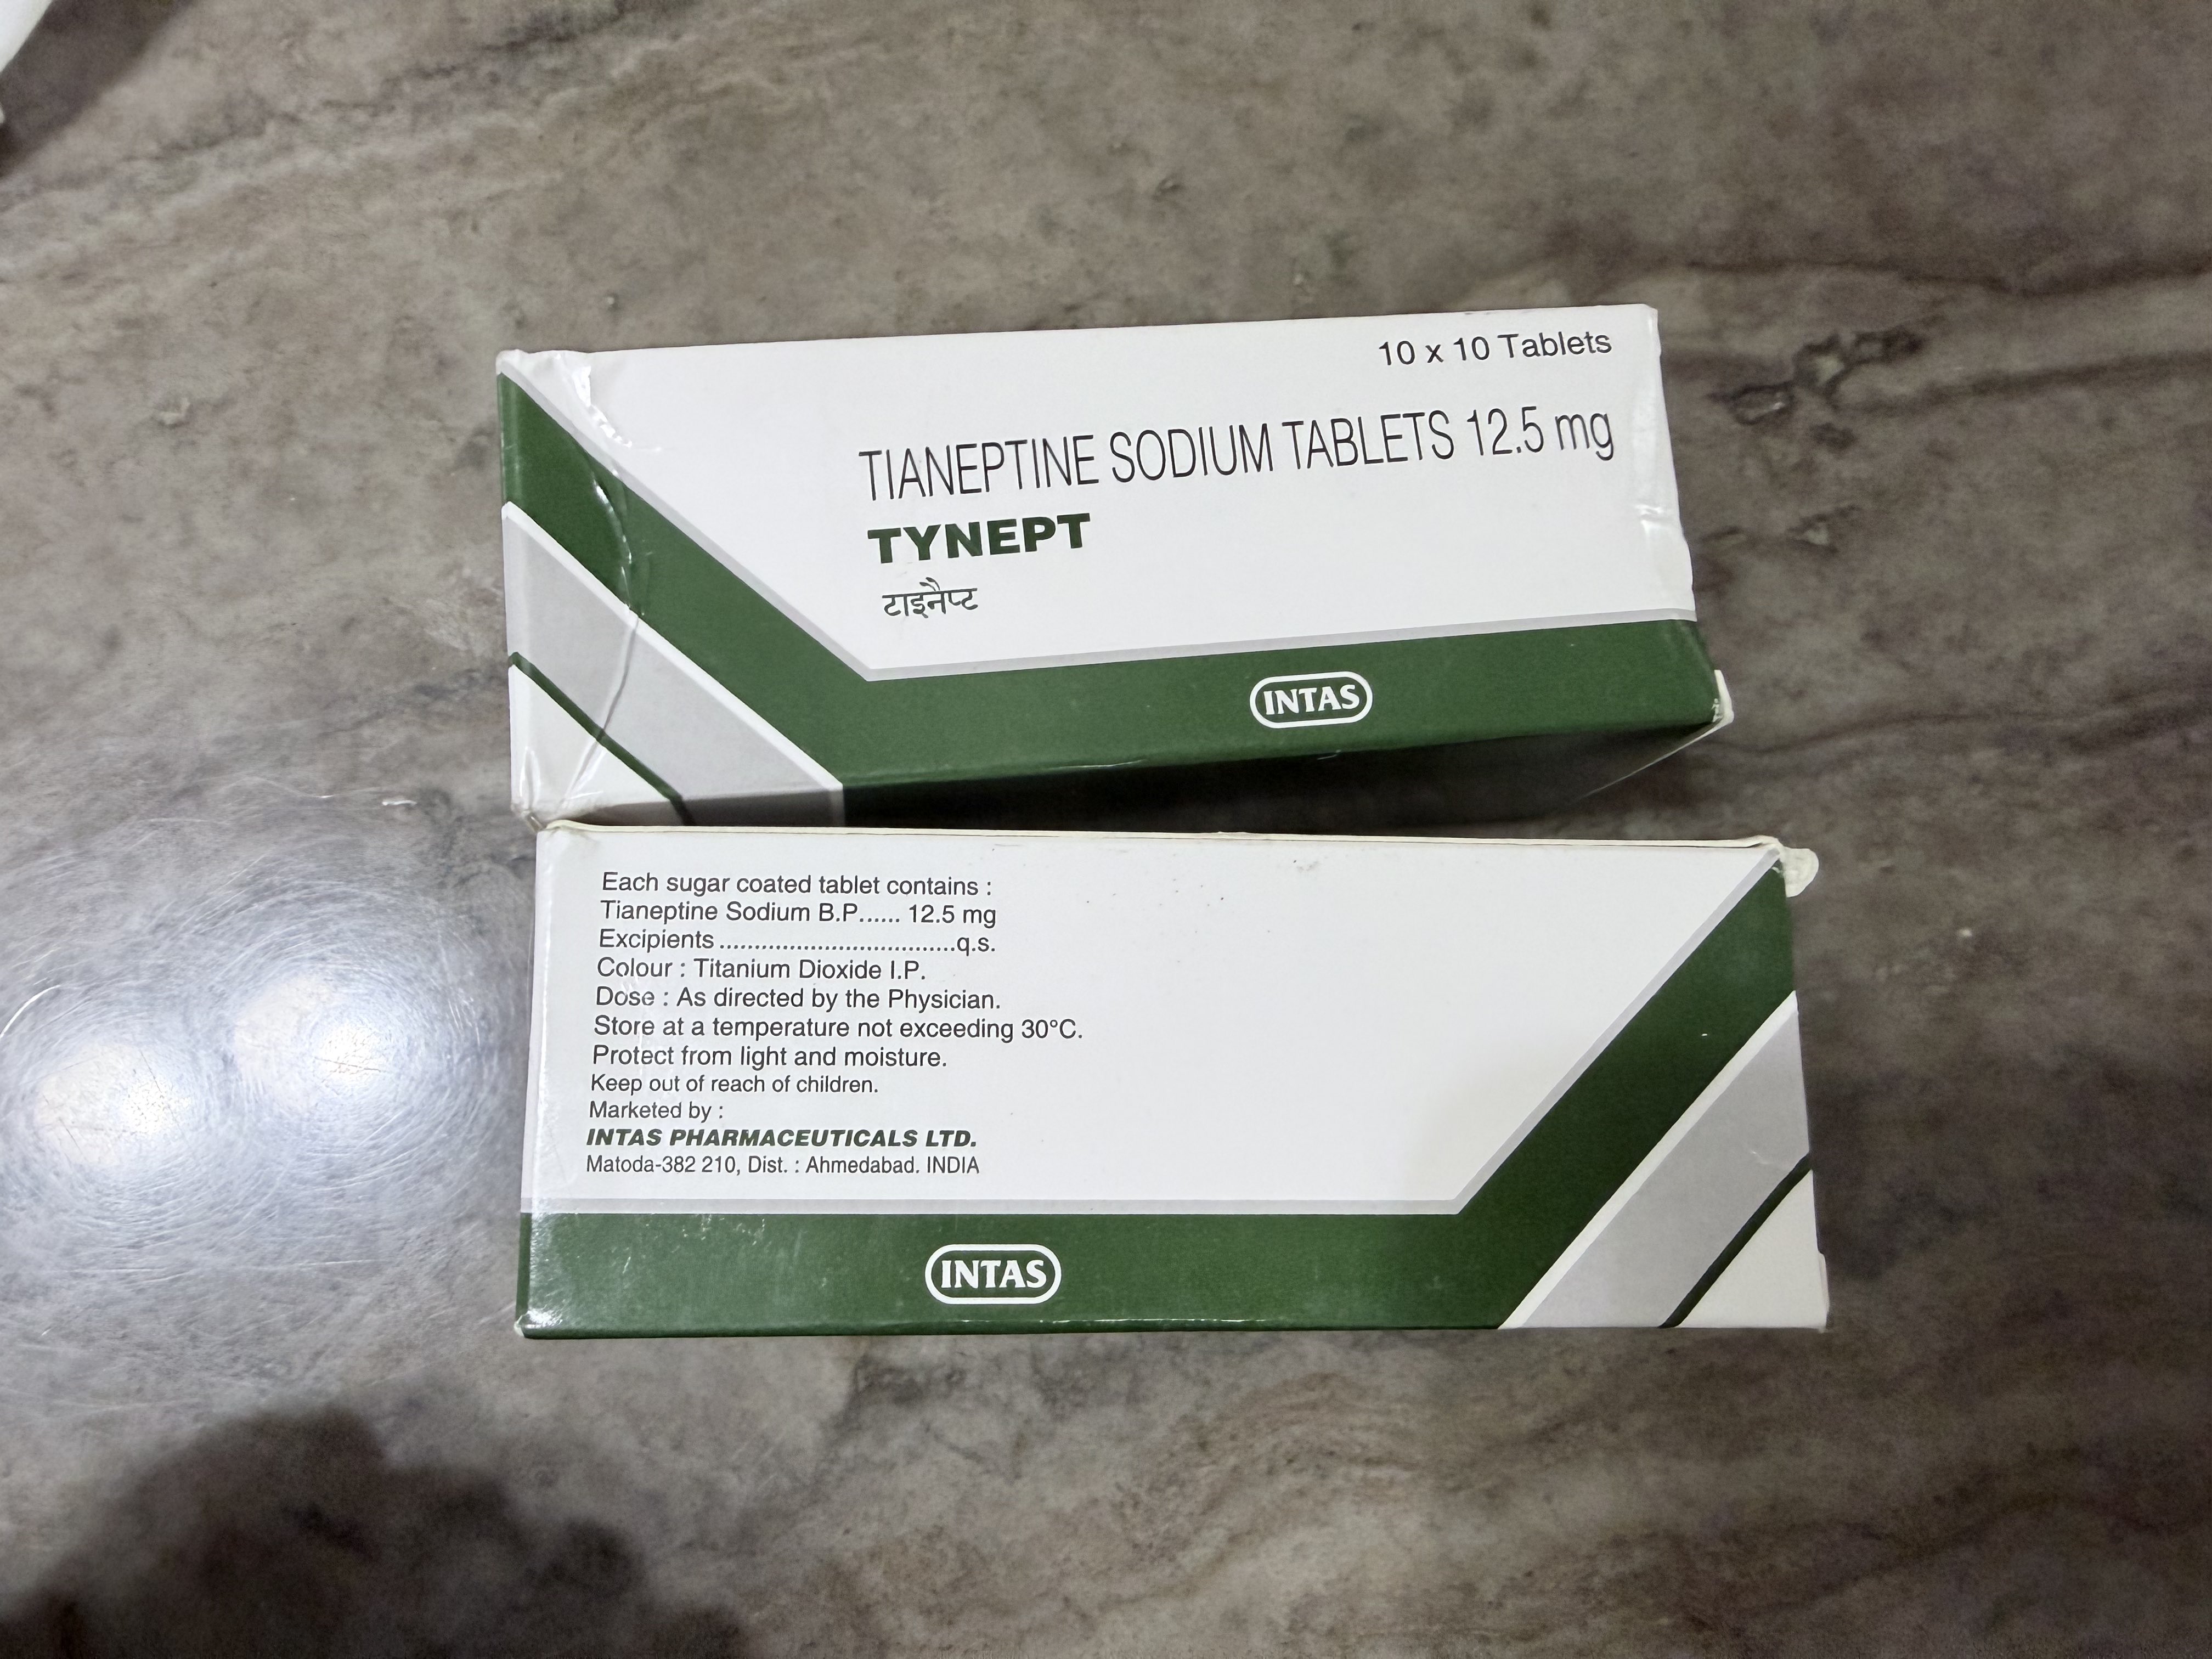

Tianeptine(半硫酸盐)

我只测试了几次相对偏高的剂量,其中一次在情绪波动很大的时候效果尤其出色,比起压制更像是一种能想通的感觉(?)

目前还没有观察到有情绪反弹的现象

但大剂量也会让延后出现的胃肠道副作用更明显,可能我又要滴定个合适的剂量范围了...哎

炽烈已极 @AnIncandescence1我测了,可能是形式不同的关系,阿片样作用并不强,反而可能是对情绪控制很有帮助,推测在日常使用有助于恢复面对现实和适应变化的能力

2025-04-11T17:57:54.000Z

意外地娱乐性不高但实用价值可能较强,因为涉及谷氨酸调节(nmda和ampa受体功能),恢复突触可塑性,还有海马神经保护(增加脑源性神经营养因子bdnf表达)

炽烈已极 @AnIncandescence阿片u+胆碱能副交感调节?

2025-04-14 18:24:11 UTC

但在抗抑郁剂量下它间接调节谷氨酸 - 胆碱能 - HPA轴反馈的机制更多是有益的,虽然说阿片这块抗抑郁的作用现在也有研究,我感觉这个药还是低剂量比较划算🤔

鼠尾草~🌿 @SalviaSWC@AnIncandescence 半硫酸盐确实比钠作用时间长,适合神经保护,不适合娱乐()

2025-04-14T22:08:01.000Z

炽烈已极 @AnIncandescence@SalviaSWC 本来我首选是钠盐的,但直觉上就是这个副作用要更恐怖一点(ó﹏ò。)💦

2025-04-15 03:28:58 UTC

鼠尾草~🌿 @SalviaSWC@AnIncandescence 钠盐作用时间太短了,好像撤药反应比较也严重()

2025-04-15T04:55:02.000Z

炽烈已极 @AnIncandescence@SalviaSWC 而且很贵!

2025-04-15 04:58:37 UTC